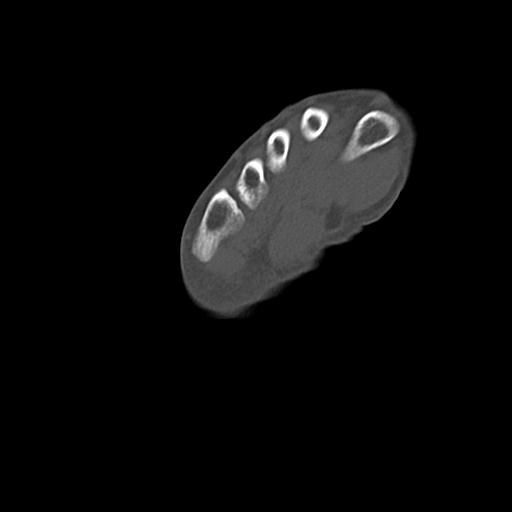

56476 8/28 4R 1/21 2R 左足関節 デジカメ写真 72歳女性 右足関節AS